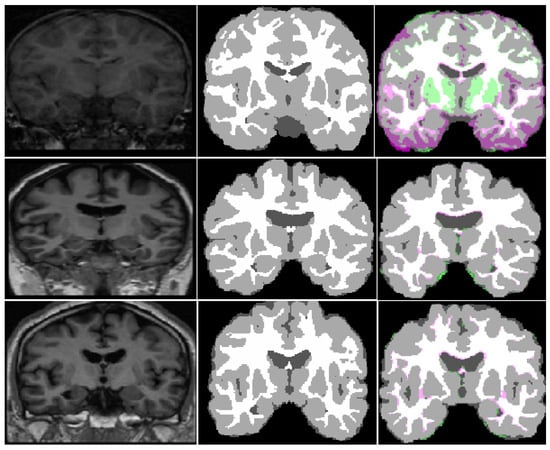

3.4.1. Results on OASIS Dataset

3.4.2. Results on IBSR18 Dataset